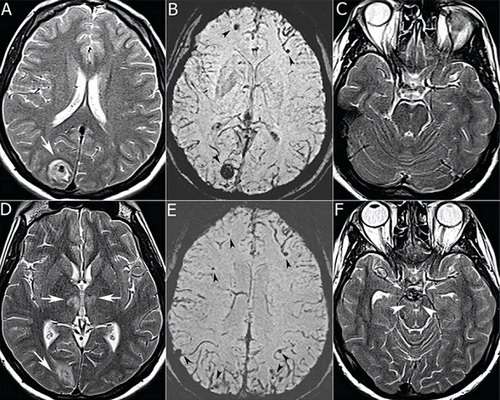

7. Ретинит, вызванный цитомегаловирусом.

Аксиальное Т1-взвешенное изображение с контрастным усилением: асимметричное утолщение сосудистой оболочки глаза справа (стрелка) по сравнению с левой стороной.

8. Каротидная кавернозная фистула.

На аксиальной Т1-взвешенной МР-томограмме визуализируется расширение правой и левой верхних глазничных вен (стрелки).